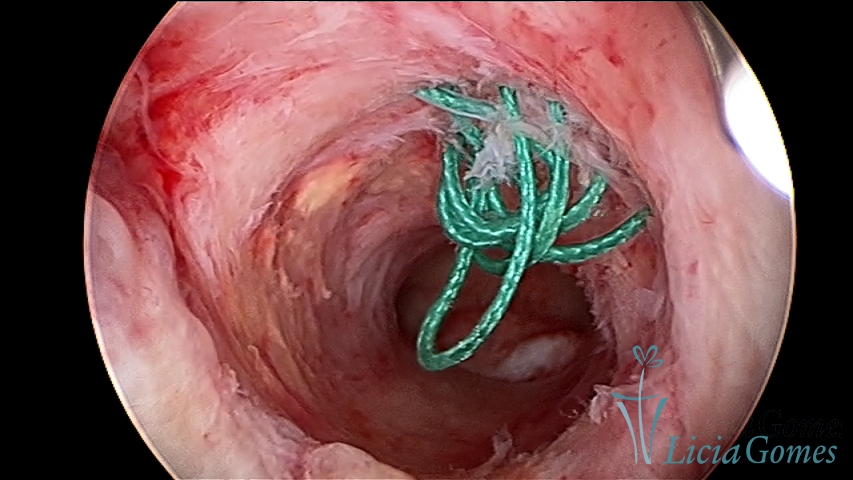

Retração da cicatriz de cesárea com fio de sutura, não absorvido, como corpo estranho